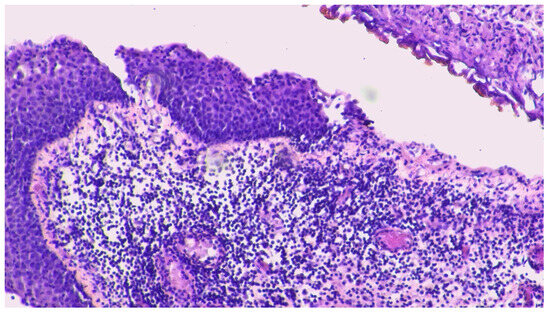

健康・医学 PCR/RT-PCRinsituLight&ElectronMicroscopy Mycoplasma ovipneumoniae - GENETIC PCR SOLUTIONS™の詳細情報

Mycoplasma ovipneumoniae - GENETIC PCR SOLUTIONS™。MgMs qPCR - vetproof Mycoplasma Gallisepticum Synoviae qPCR。Metabolic Complete Response of Metastatic Oncogene-Negative。PCR/RT- PCR in situ Light and Electron MicroscopyBy Mireille RaccurtCopyright Year 2002ISBN 9780849300417Published September 27, 2002 by CRC Press432 Pages 21 Color & 237 B/W Illustrationsご覧いただきありがとうございます。Programmed Death-Ligand 1 Copy Number Loss in NSCLC。ご検討いただけますと幸いです。看護がみえる vol.1〜4 4冊セット。何卒よろしくお願いいたします。いきなり帝王切開術 局所解剖を熟知し,コツを盗もう(OGS NOW basic)。